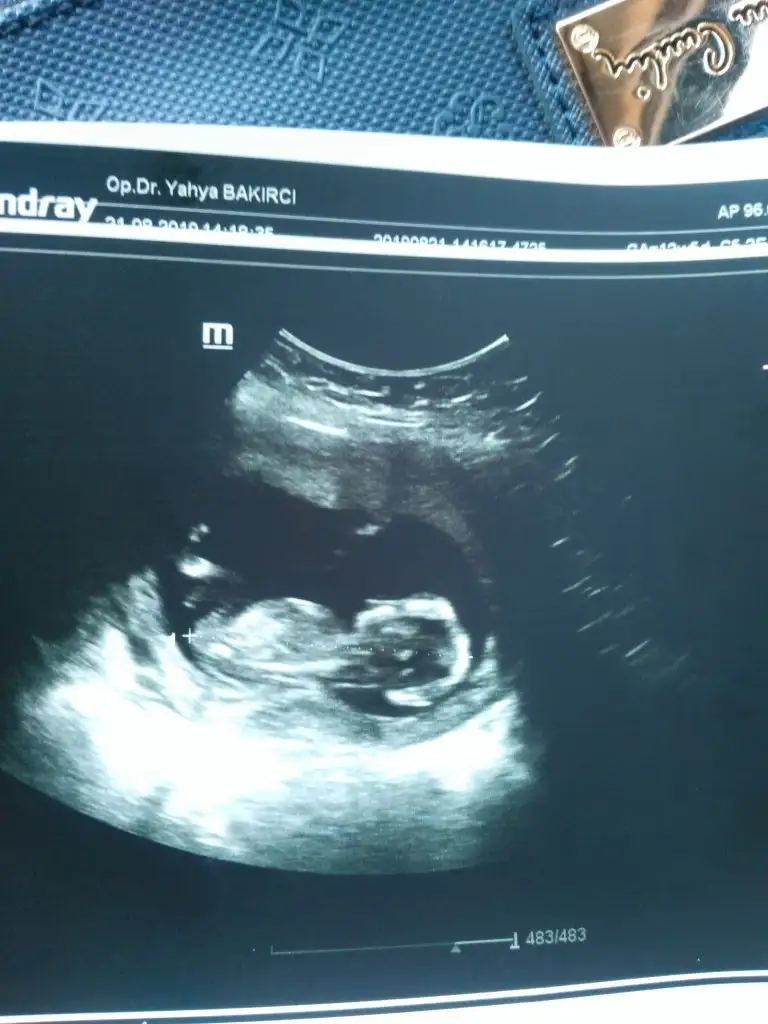

tesekkur ediyorum bakip yorunladiginiz icin ogrenir ogrenmez yazicamBurda nub çizgisi dik değil paralel gibi duruyor yani kız gibi ama kafa yapısı erkeğe çok benziyor.ben yine erkekten yana kullanıyorum oyumu

Başka usg varmı hafif sırta dönükIkra meyra fotoya sen de bakar misin